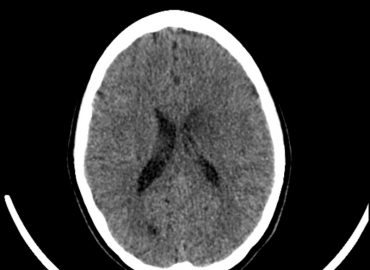

Paciente: femenina de 9 meses de edad Motivo de consulta: episodios convulsivos.

Niña de 5 años de edad, debut de crisis convulsiva.